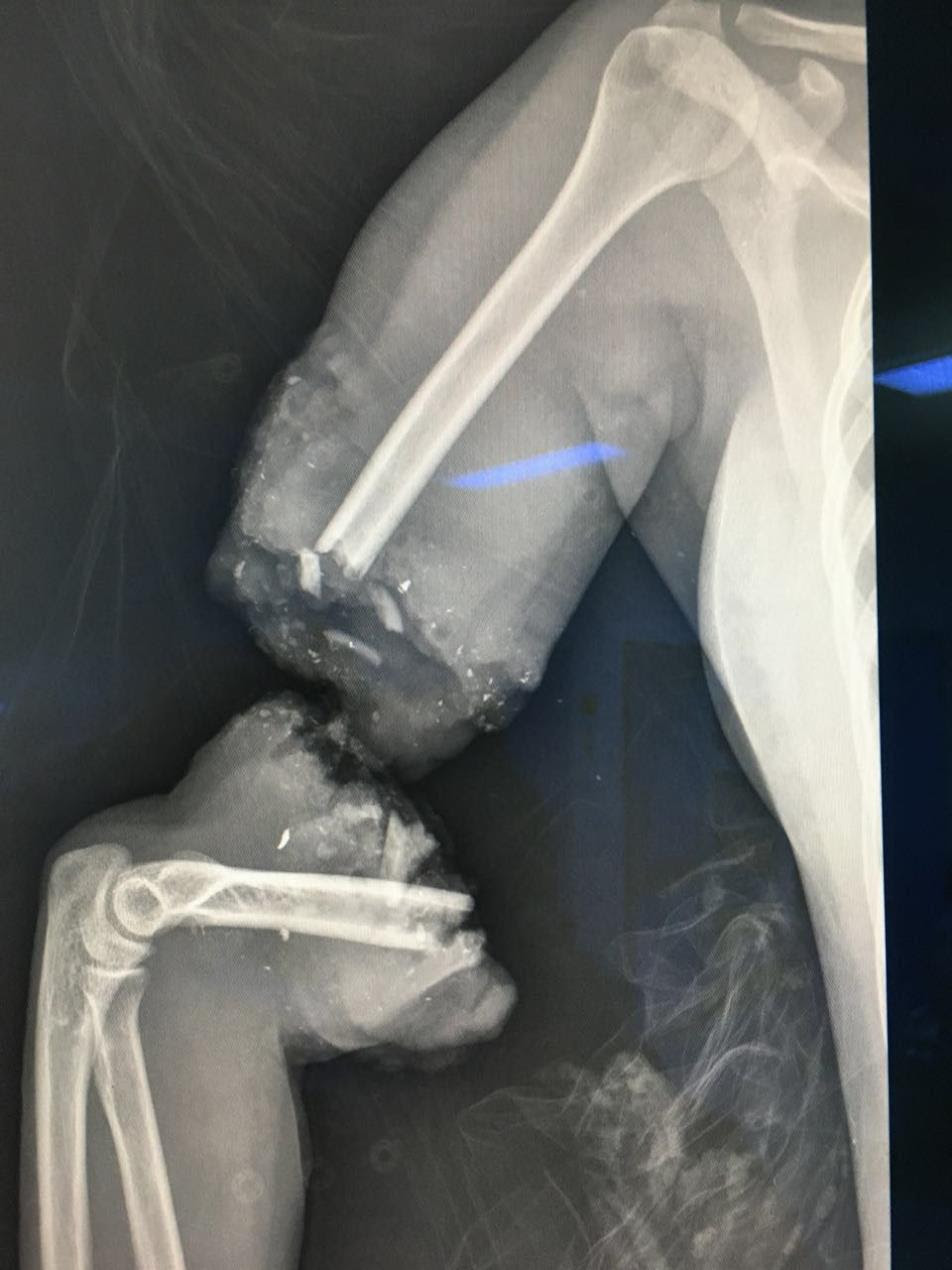

Riyadh: A surgical team at King Abdulaziz Hospital in Jeddah (western Saudi Arabia) was able to save a pregnant woman and her fetus after enduring a serious run-over accident while crossing a busy street on Tuesday 27th Sep, which led to the amputation of her entire arm.

Saudi Health indicated that the patient came to the hospital’s emergency as a critical case that requires saving the mother and the fetus. A rapid response medical team was set, and surgery was performed to restore the amputated limb in a procedure that lasted for 6 hours, which ended with returning the arm to full functionality.